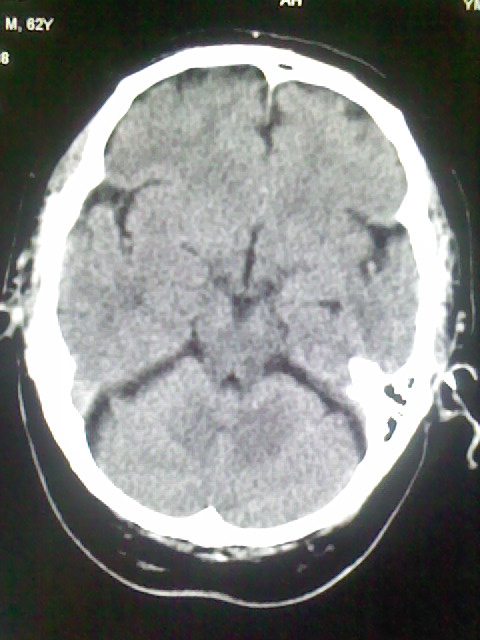

标题: CT15555:头痛 10余日 来诊大家帮忙看看 [打印本页]

标题: CT15555:头痛 10余日 来诊大家帮忙看看

脑沟、裂增宽,提法脑萎缩,建议mt检查。

脑萎缩,以小脑为著。

脑沟、裂增宽,提示脑萎缩

老年脑

支持轻度脑萎缩。